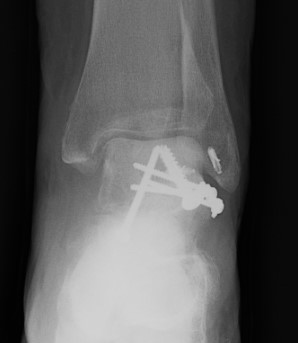

Cannulated screws

Xrays

| AP | Lateral | Canale View |

|---|---|---|

| Entry point of the screws |

Evaluate neck reduction

|

Evaluates the neck reduction |

Lateral off articular surface Medial through articular cartilage |

Depth of screws |

Beam angled 75o to foot Foot 15o pronated |

Plates

Options

- mini fragment plates

- anatomically contoured talar neck plates

- lateral talar neck very curved

Screw + plate